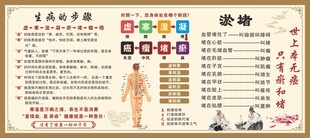

中医经络穴位知识图表 共享分:40

中医经络穴位知识图表 共享分:40 -